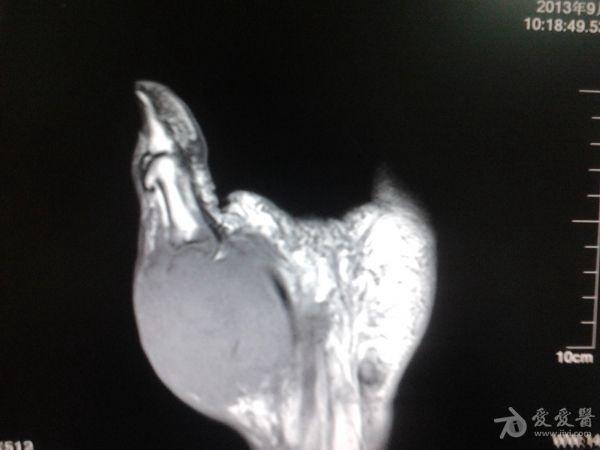

右第一掌骨、大多角骨肿瘤

男性患者,81岁,右手肿痛3个多月。无任何其它症状。体查:右手第一掌骨部肿胀明显,第一指活动受限,余四指活动可,腕关节活动小部分受限,活动时会痛。影像学检查如下。活检示:弥漫性大B细胞淋巴瘤。大家看看需不需要截肢?现在有人主张手术;有人主张不手术,直接化疗。大家有什么看法?

从以上资料看已经影响到腕关节了,还是截吧,不能姑息